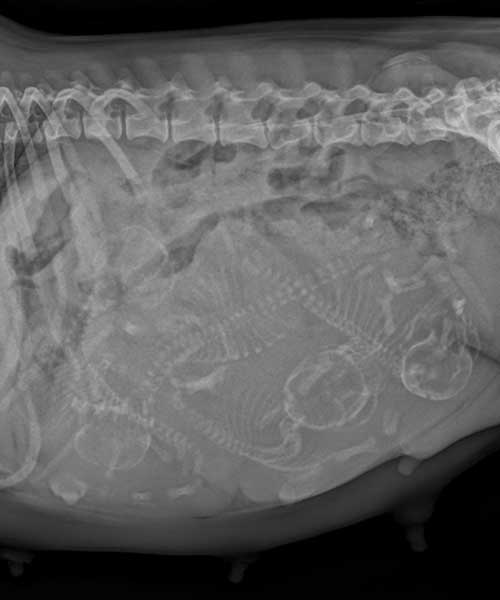

La radiographie abdominale

La radiographie de l'abdomen permet de rechercher les pathologies du système digestif ou urinaire.

Elle permet de diagnostiquer par exemple des objets avalés (comme des cailloux ou des jouets), des torsions d'organes, des déplacements, la présence de liquide ou d'air, des tumeurs ou bien des calculs urinaires.